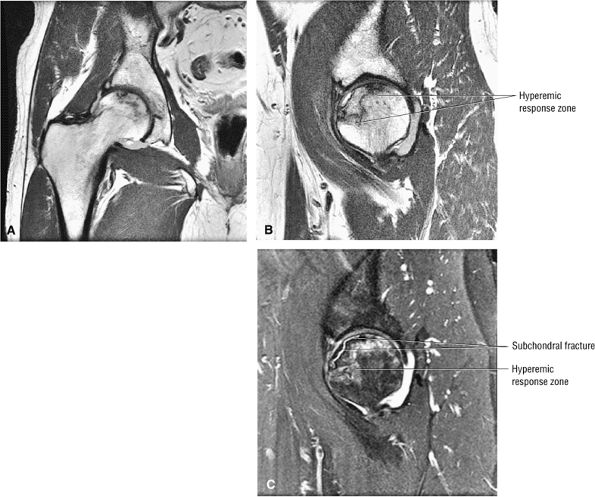

FIGURE 3.88 ● Post-core decompression for an ischemic focus with associated subchondral fracture without femoral head collapse. Arthroscopy has been performed for stage IV or post-collapse patients who are also candidates for osteotomy or vascularized graft. Delamination of articular cartilage is treated with débridement and core decompression, although improvement may be limited. (A) Coronal T1-weighted image. (B) Sagittal FS PD FSE image.

|